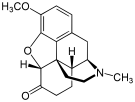

Morphinones and morphols

Structures

| Morphinones and morphols | ||||

|---|---|---|---|---|

14-Cinnamoyloxycodeinone 14-Cinnamoyloxycodeinone |

14-Ethoxymetopon 14-Ethoxymetopon |

14-Methoxymetopon 14-Methoxymetopon |

14-Phenylpropoxymetopon 14-Phenylpropoxymetopon |

7-Spiroindanyloxymorphone 7-Spiroindanyloxymorphone |

8,14-Dihydroxydihydromorphinone 8,14-Dihydroxydihydromorphinone |

Acetylcodone Acetylcodone |

Acetylmorphone Acetylmorphone |

α-hydrocodol α-hydrocodol(Dihydrocodeine) |

Bromoisopropropyldihydromorphinone Bromoisopropropyldihydromorphinone |

Codeinone Codeinone |

Codorphone Codorphone |

Codol Codol(Codeine Phosphate) |

Codoxime Codoxime |

IBNtxA IBNtxA |

Thebacon Thebacon |

Hydrocodone Hydrocodone |

Hydromorphone Hydromorphone |

Hydroxycodeine Hydroxycodeine |

Metopon Metopon(methyldihydromorphinone) |

Morphenol Morphenol |

Morphinone Morphinone |

Morphol Morphol |

N-Phenethyl-14-ethoxymetopon N-Phenethyl-14-ethoxymetopon |

Oxycodone Oxycodone |

Oxymorphol Oxymorphol |

Oxymorphone Oxymorphone |

Pentamorphone Pentamorphone |

Semorphone Semorphone |